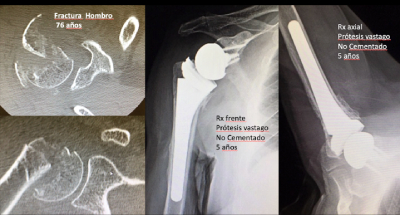

Un assaig clínic d'alt nivell metodològic ha demostrat que una configuració específica de la pròtesi reversa d'espatlla afavoreix de manera significativa la consolidació de la tuberositat més gran en pacients grans amb fractures complexes de l'húmer proximal, una lesió molt freqüent a la població d'edat avançada.

L'assaig controlat aleatoritzat va incloure 78 pacients més grans de 65 anys i va comparar dues configuracions de l'implant (155° distalitzada i 135° lateralitzada). La configuració 155° va mostrar una taxa de consolidació significativament més gran en els punts de seguiment a 6, 12 i 24 mesos, mentre que el risc de manca de consolidació va ser quatre vegades més gran en el disseny de 135°.

L'estudi també analitza característiques de l'implant que poden influir en la recuperació, com la combinació d'una tija humeral rectangular no cimentat i sense cargols, dissenyada per permetre una reconstrucció més anatòmica i resultats més consistents en pacients grans.

Les dades obtingudes recolzen el paper de la fixació no cimentada en aquest context clínic: "El nostre treball demostra que la tija humeral no cimentada en la pròtesi reversa proporciona més estabilitat inicial, facilita la consolidació dels tubercles i s'associa a millors resultats funcionals i menor taxa de complicacions. A la pràctica, això implica cirurgies més segures i predictibles, una recuperació més ràpida i una fiabilitat més gran de la pròtesi reversa en pacients grans", conclou.